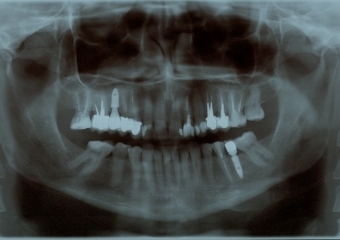

Rx Panoramico Inicial 24-07-15 - Clínica Cliniface

Rx Panoramico Inicial 24-07-15